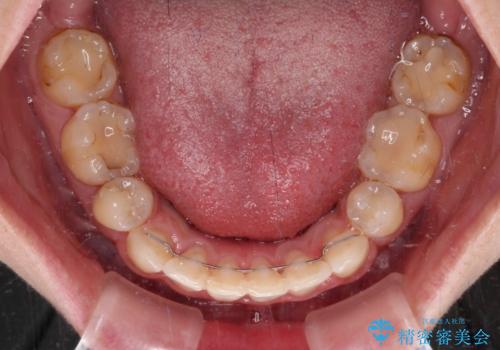

上下前歯の距離が大きかったため、上下の歯が接触するまでに時間がかかりました。

それでも目安である2年半で終えることができ、患者様には大変満足していただけました。